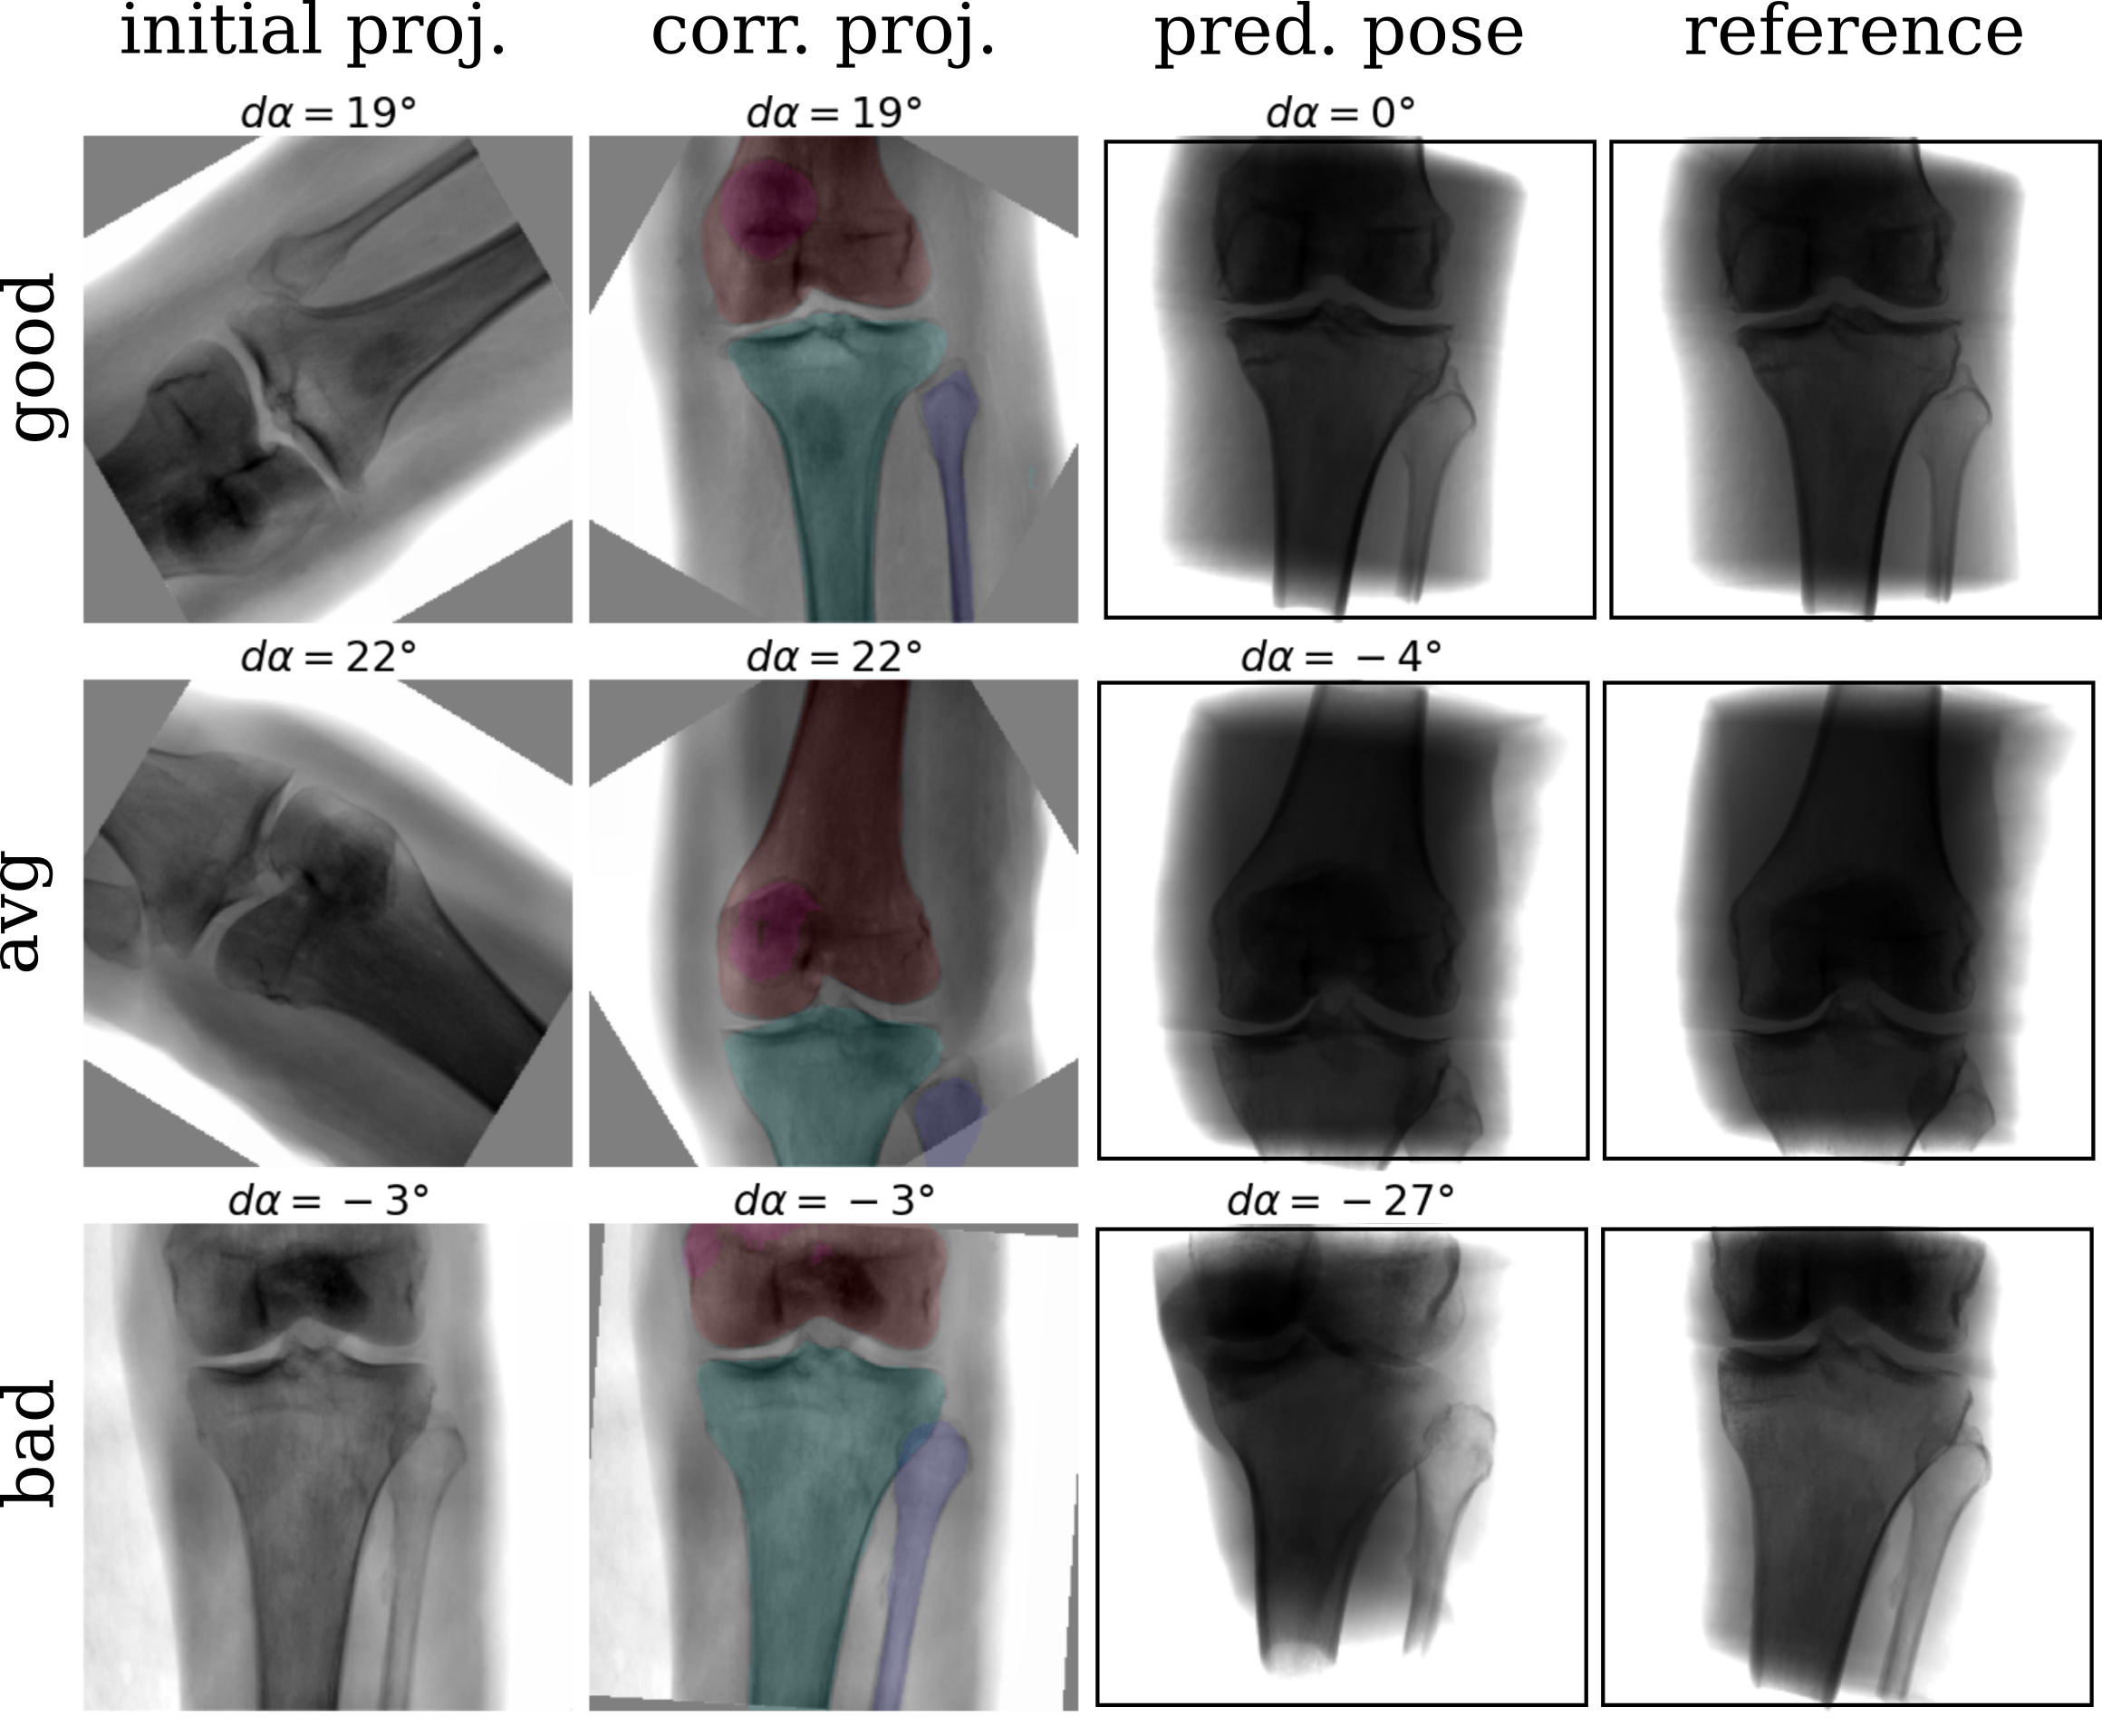

In an ablation study, the proposed shape-based view-independent pose regression was compared to view-specific direct intensity-based pose regression [11]. Further, the complete pipeline (2-step) is compared to a 1-step segmentation-based approach trained view-specific and view-independent (Fig. 4). Evaluation was performed on the simulated test DRRs and cadaveric X-rays (Fig. 5).

View-independent vs. view-specific networks: While the view-specific networks perform significantly better (lateral) or comparable (a.-p.) on the simulated data, the view-independent networks perform significantly better (a.-p.) or comparable (lateral) on the real data.

1-step vs. 2-step: The proposed 2-step approach performs significantly better or comparable than a 1-step shape-based pose regression approach on most validation cases (8/12) in viewing direction . Regarding the rotation, the 2-step approach improves performance across all validation cases.

Generalization from DRR to X-ray: The shape-based pose regression network combined with joint view-independent training clearly boosts the performance compared to direct intensity-based pose regression from to .

A complete framework for automatic acquisition of standard views of the knee is proposed that can handle several standard views simultaneously. The complete pipeline is trained on simulated data with automatically generated annotations and evaluated on real intraoperative X-rays. To bridge the domain gap, different augmentation strategies are suggested that address intraoperative confounding factors, e.g., the OR table. View-independent training and multi-label shape features improve the generalization from simulated training to real X-rays and outperform direct intensity-based approaches. View-independent networks result in more training data which showed to improve the generalization from simulated training to real X-rays. The 2-step approach increases robustness and simultaneously automates necessary preprocessing tasks like laterality and standard view recognition, which can be performed with very high accuracy on simulated (, ) and real data (, ). The approach is fast and easy to translate into the operating room as it does not require any additional technical equipment. Assuming that the surgeon acquires the initial X-ray with a pose offset within the capture range of , it has the potential to reduce time and unnecessary radiation during manual C-arm positioning. Furthermore, the segmentation features can serve as a sanity check and indicate the reliability of the pose regression result. Further experiments with a larger training set covering more anatomical variation, e.g., patella baja and different flexion angles [13], can potentially address observed failure cases.